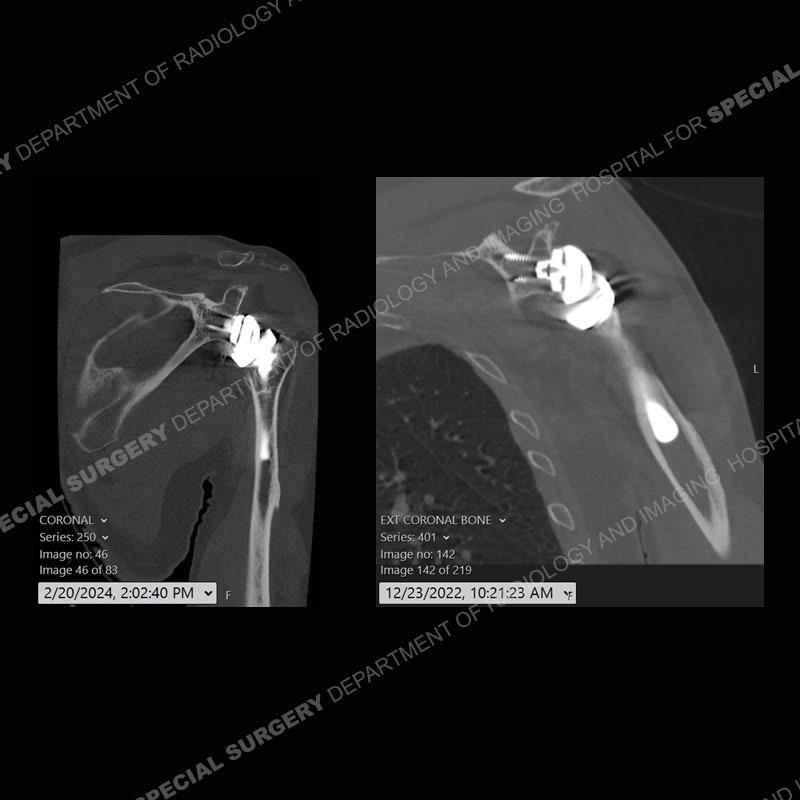

When comparing the radiographs, there is a slight change in the alignment in the components of the prosthesis. On the current radiographs, a radiolucent, crescentic focus is present at the level of the glenoid. When comparing the CT exams, there is a change at the alignment of the glenosphere and the humeral component and now a direct apposition of the components. On the current CT, the radiolucent, crescentic focus is again identified.

If comparison radiographs are present, subtle changes can be made more apparent. Instead of a space between the glenosphere and the humeral tray, there is a direct contact, and there may be an overall change in the alignment at the articulation. The displaced, radiolucent polyethylene liner depending on location can be seen on the radiographs, as in this case. At times, the liner may overlie other structures making identification very difficult on radiographs, but it should almost always be able to be identified on CT (as shown in this example as well). This patient is scheduled for revision procedure.